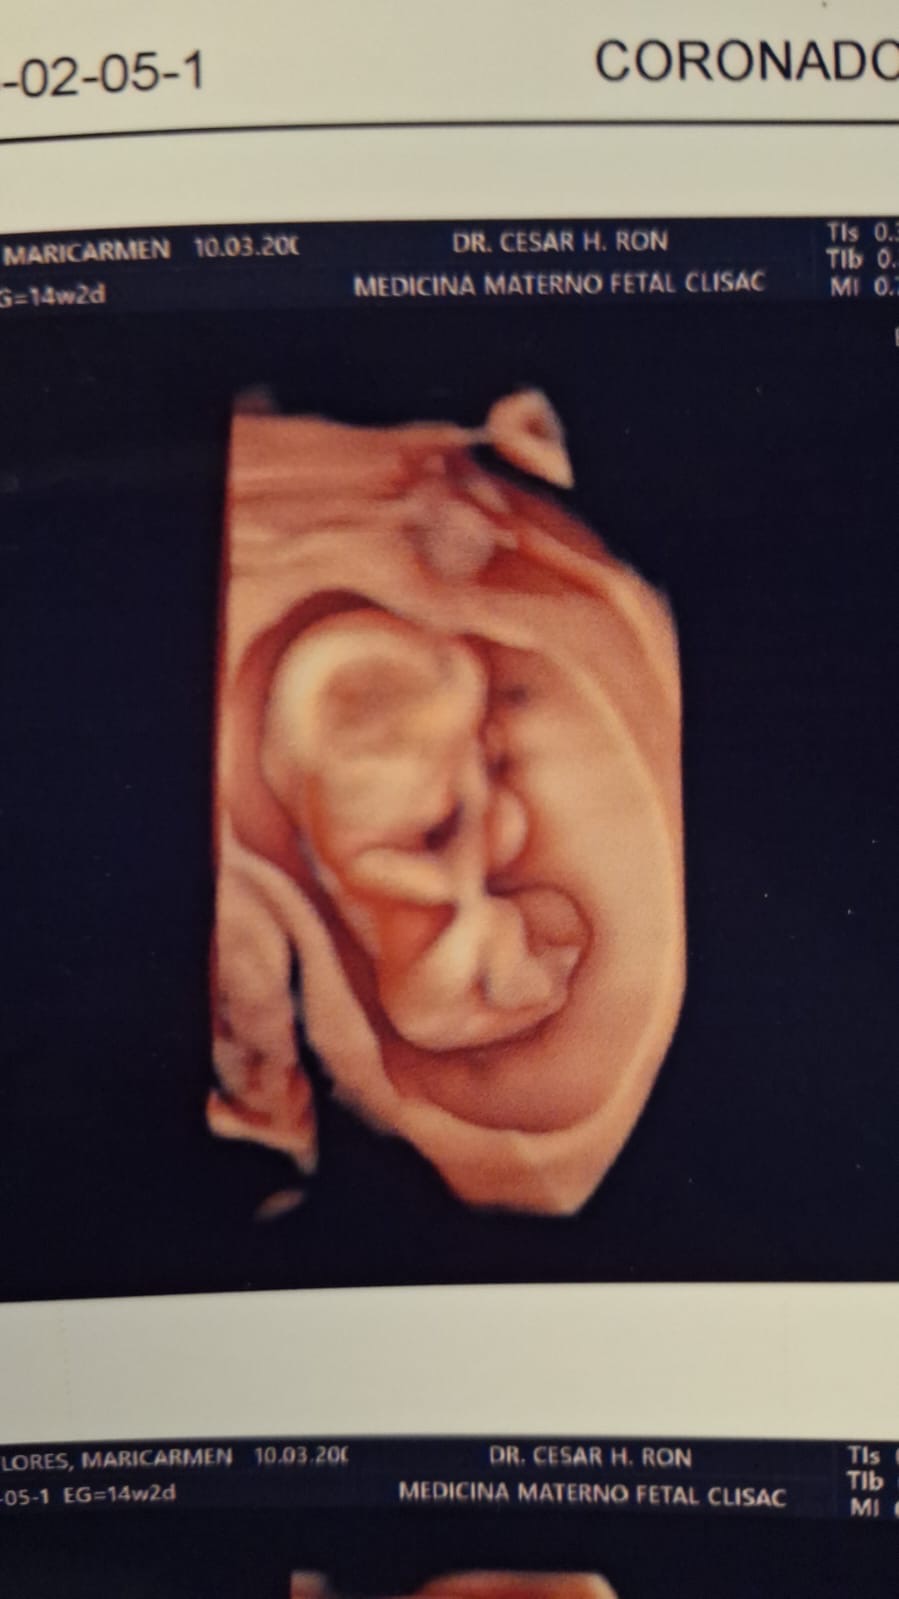

Hola mi nombre es Einar Nicolás y aún me encuentro en la pancita de mamá, hace poco me diagnosticaron una condición llamada Pentalogía de Cantrell lo que provoca que mi hígado, intestino y corazón se desarrollen fuera de mi cuerpo. Mamá y Papá descubrieron una clínica donde pueden atender esta condición y darme una oportunidad de vida, pero estas cirugías que necesito son muy costosas por eso están recaudando fondos. ¡Gracias por tu ayuda!

Hello, my name is Einar Nicolás and I'm still in mom's belly, I was recently diagnosed with a condition called Cantrell's Pentalogy which causes my liver, intestine and heart to develop outside my body. Mom and Dad discovered a clinic where they can take care of this condition and give me a chance at life, but these surgeries I need are very expensive that's why they're raising funds. Thank you for your help!